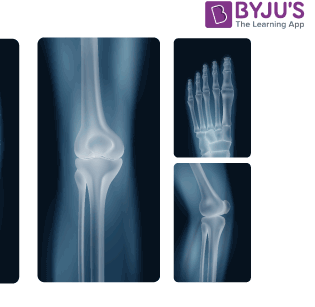

X-rays are a form of electromagnetic radiation, much like visible light, but with much higher energy levels. The key distinction is that X-rays have enough energy to pass through various materials, including the human body, which makes them ideal for medical imaging. When directed through the body, X-rays are absorbed by different tissues to varying degrees. Dense materials, like bones, absorb more radiation and appear white on X-ray films, while softer tissues, like muscles and organs, appear darker.

The process of taking an X-ray image involves sending a controlled beam of X-rays through the body, which are then absorbed by the tissues in the body. The X-rays that pass through the body hit a special detector or film on the other side, creating a shadow-like image. The differences in the absorption of X-rays by different body parts create a clear contrast, allowing healthcare professionals to view the internal structures of the body.

Bone Fractures and Injuries

The most common use of X-rays is for detecting bone fractures and injuries. The contrast between bones and surrounding tissues makes fractures easily identifiable.Dental X-rays